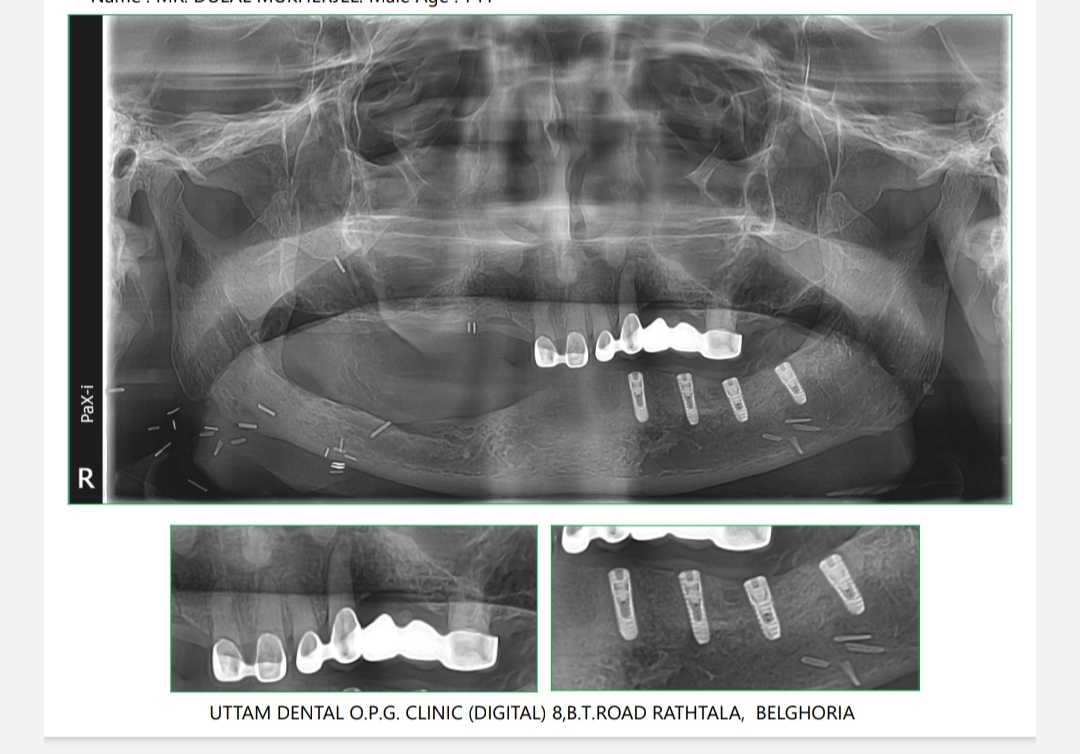

Dental implants are long-term investment in oral health. Unlike other tooth replacement options, such as dentures or bridges, dental implants can last a lifetime with proper care and maintenance. They do not require any special cleaning or adhesives, and they do not put strain on adjacent teeth like bridges can.